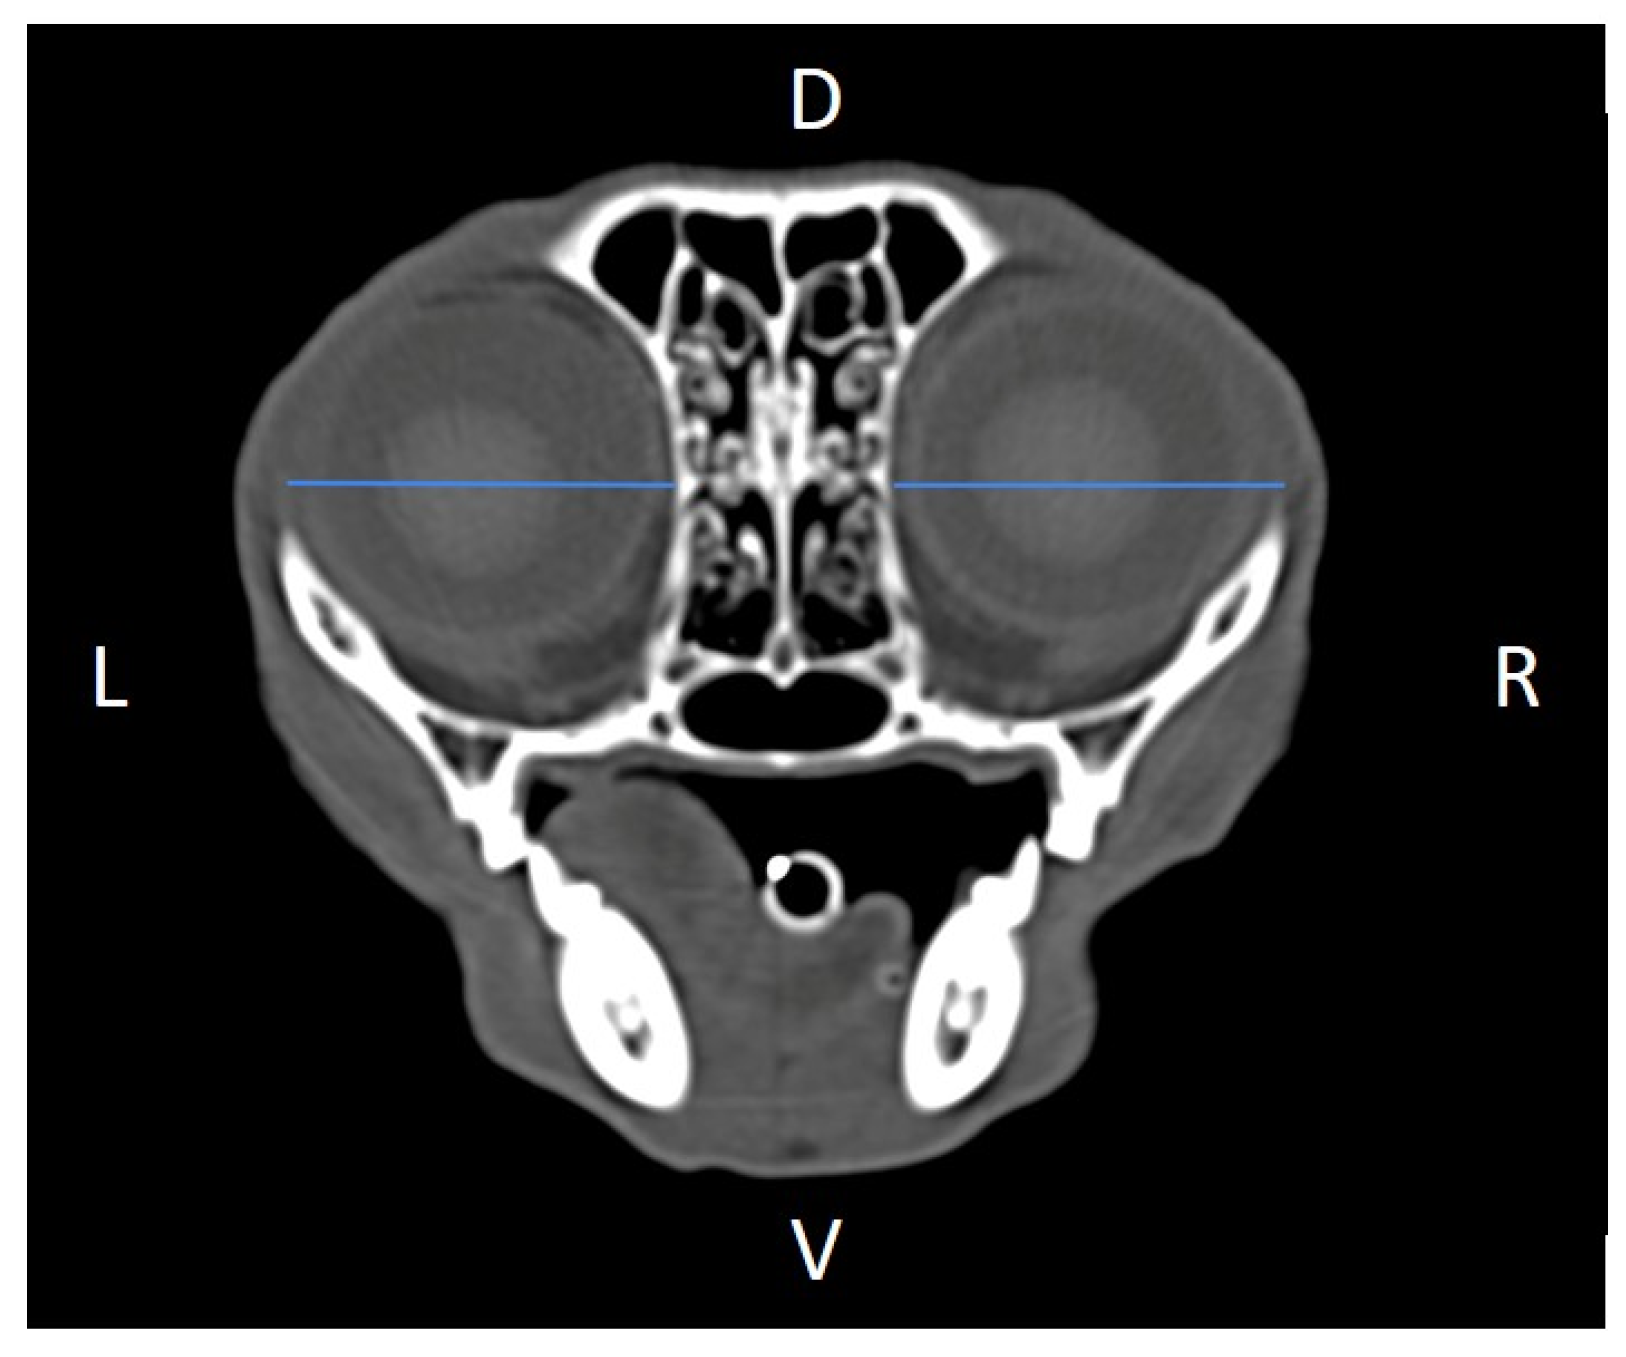

Linear morphometric parameters (Table 1) were obtained directly from CT images using HorosTM v3.3.6.dmg DICOM software with bone filters. Prior to measurement, all images were calibrated from pixels to millimeters. A preliminary study and prior training were conducted, to establish anatomical landmarks that would allow for the repeatability of the measurement methodology by J.F.R., A.R.S., S.A.-P. Recorded variables included infraorbital foramen major axis (Figure 2), minor axis (Figure 3) and length (Figure 4), distance between infraorbital foramina (DIF) (Figure 5), orbital height and width (Figure 6 and Figure 7), zygomatic arch width (Figure 8), skull width and length (Figure 9). Ratios were calculated to normalize for skull size. As preliminary results revealed adequate repeatability of measurements, and in order to reduce the analysis margin of error, two measurements of each studied parameter were performed. The measurements were performed by the same operator (to reduce interpersonal errors), and each measurement of each parameter was performed at different times, in order to reduce intrapersonal errors. Then, the arithmetic mean of the measurements was calculated.

Figure 7. Orbital width (OW) measured at the left and right sides, on a transverse CT image (blue lines). D, dorsal, L, left, R, right, V, ventral.